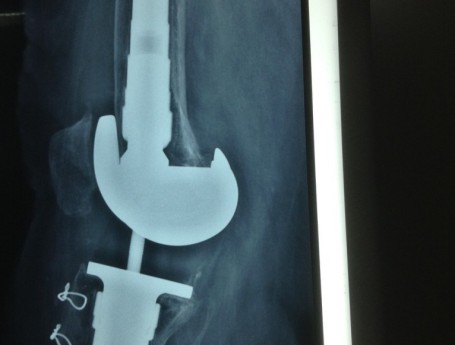

Revision Total Knee Replacement After a fructure

• Revision Total Knee Replacement After a fructure